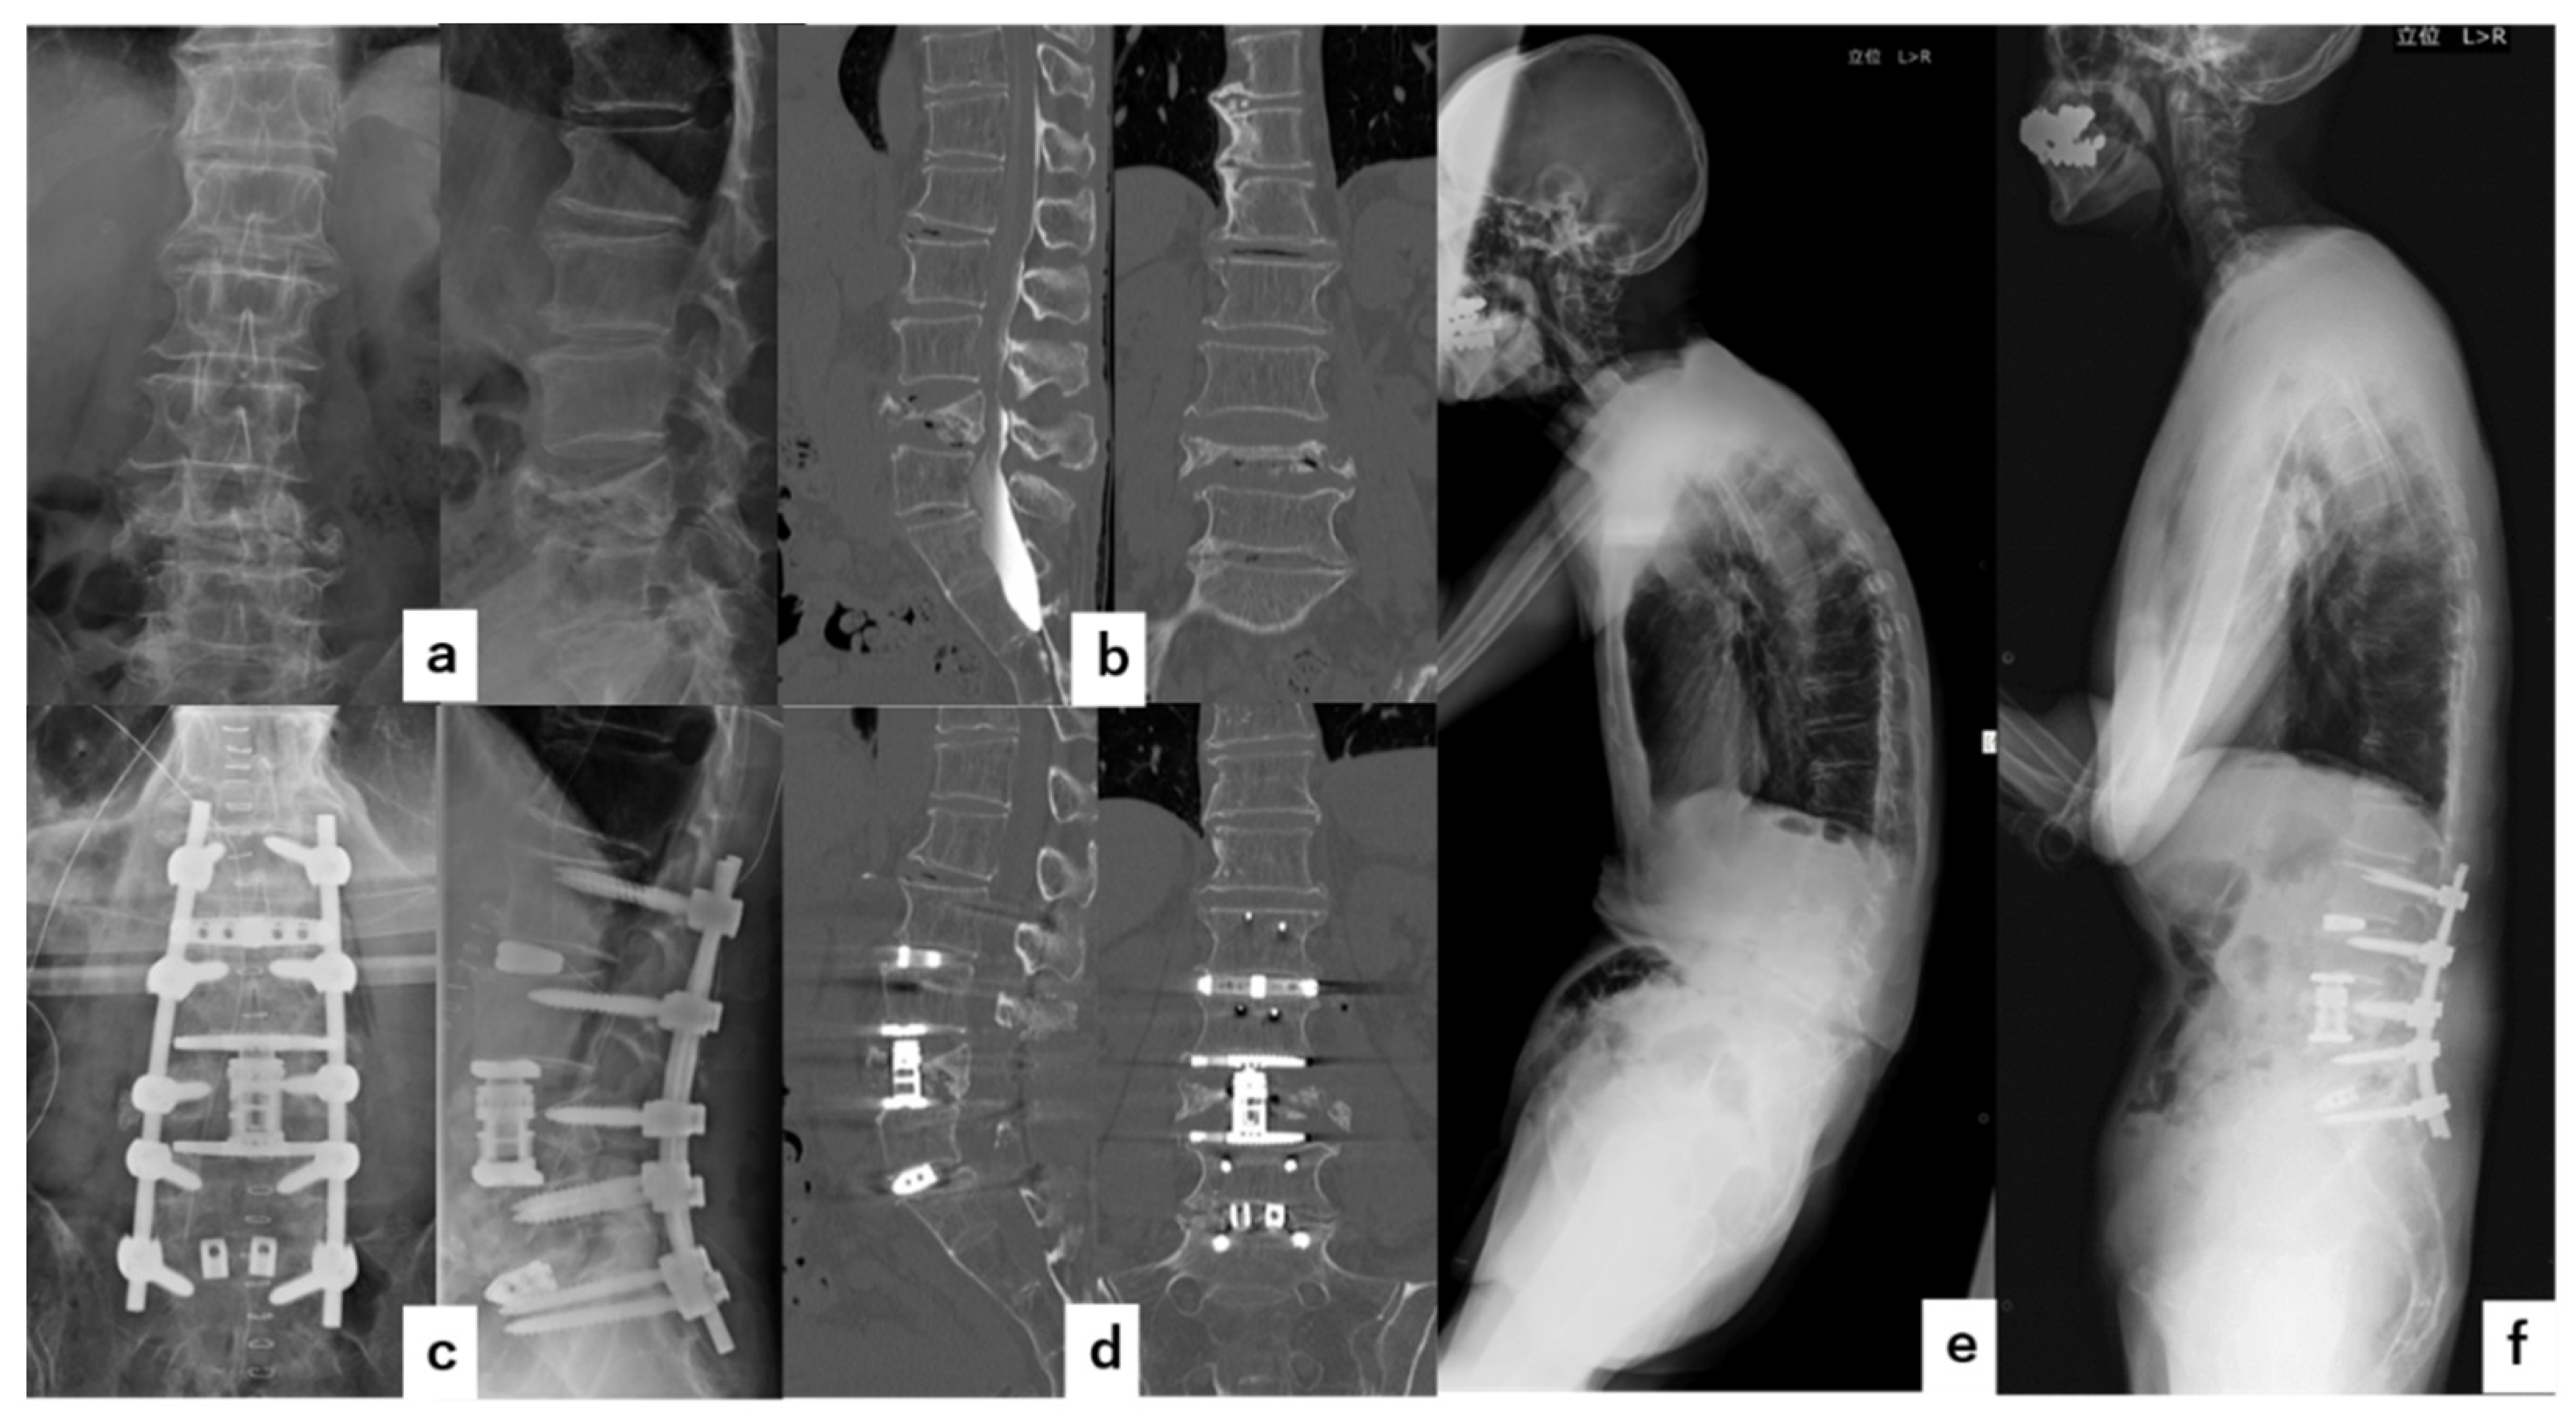

4. Illustrative Cases

4.1. Case 1

4.2. Case 2